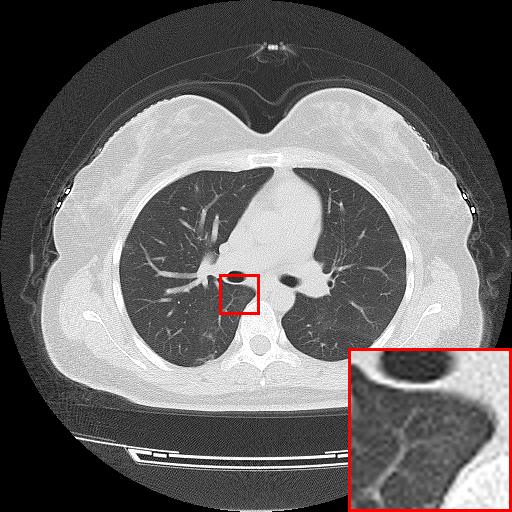

Figure 6: Reconstruction results of each algorithm for low-doze chest CT images.

III-D Super-resolution Reconstruction of Low-dose CT images

Medical pictures, such as computed tomography (CT) scans, are widely used in clinical applications such as noninvasive illness detection, anatomical imaging, and treatment planning, all of which need judgment while doing CT scans. These imaging approaches, however, have some drawbacks. During CT scans, for example, radiation damage is unavoidable. Low-dose CT (LDCT) is currently the clinically recommended strategy for preventing irreversible radiation harm to the body, however it comes at the cost of getting CT pictures with low resolution or noise contamination. The spatial resolution is generally coarser than that of CT imaging in order to get images with a high signal-to-noise ratio. As a result, obtaining high-resolution scanned images with a low-dose CT scanner is now a challenge.

In this section, we selected chest CT images of COVID-19 patients in an actual hospital [26] for our experiments. The visualization results of the experiments are shown in Figure 5 and Figure 6. The experimental results show that our proposed T-GAN is also applicable to the super-resolution reconstruction of low-dose CT images, and the high-resolution images obtained by our model have more detailed information compared with the baseline algorithm.